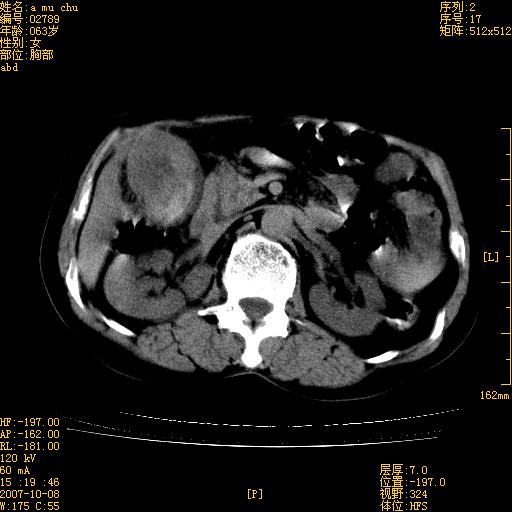

以下是引用王维浦在2007-10-17 21:02:00的发言:[br]胆囊增大,囊壁明显不规则增厚,邻近肝组织浸润,肝内外胆管无扩张。诊断:胆囊ca;[br]胰头软组织肿块影,考虑是由转移肿大的胰后淋巴结、没有肠道准备的十二指肠及胰头共同形成。[br]

以下是引用zhangzexing在2007-10-18 7:13:00的发言:[br]支持胰头占位,慢性胆囊炎. 2.肝左叶前外侧段占位,血管瘤?建议增强

以下是引用影像实习生在2007-10-17 19:49:00的发言:[br]支持胰头占位,慢性胆囊炎. 2.肝左叶前外侧段占位,血管瘤?建议增强.

以下是引用刘振江在2007-10-17 19:42:00的发言:[br]没有增强,胰头癌?胆囊及肝左叶占位?